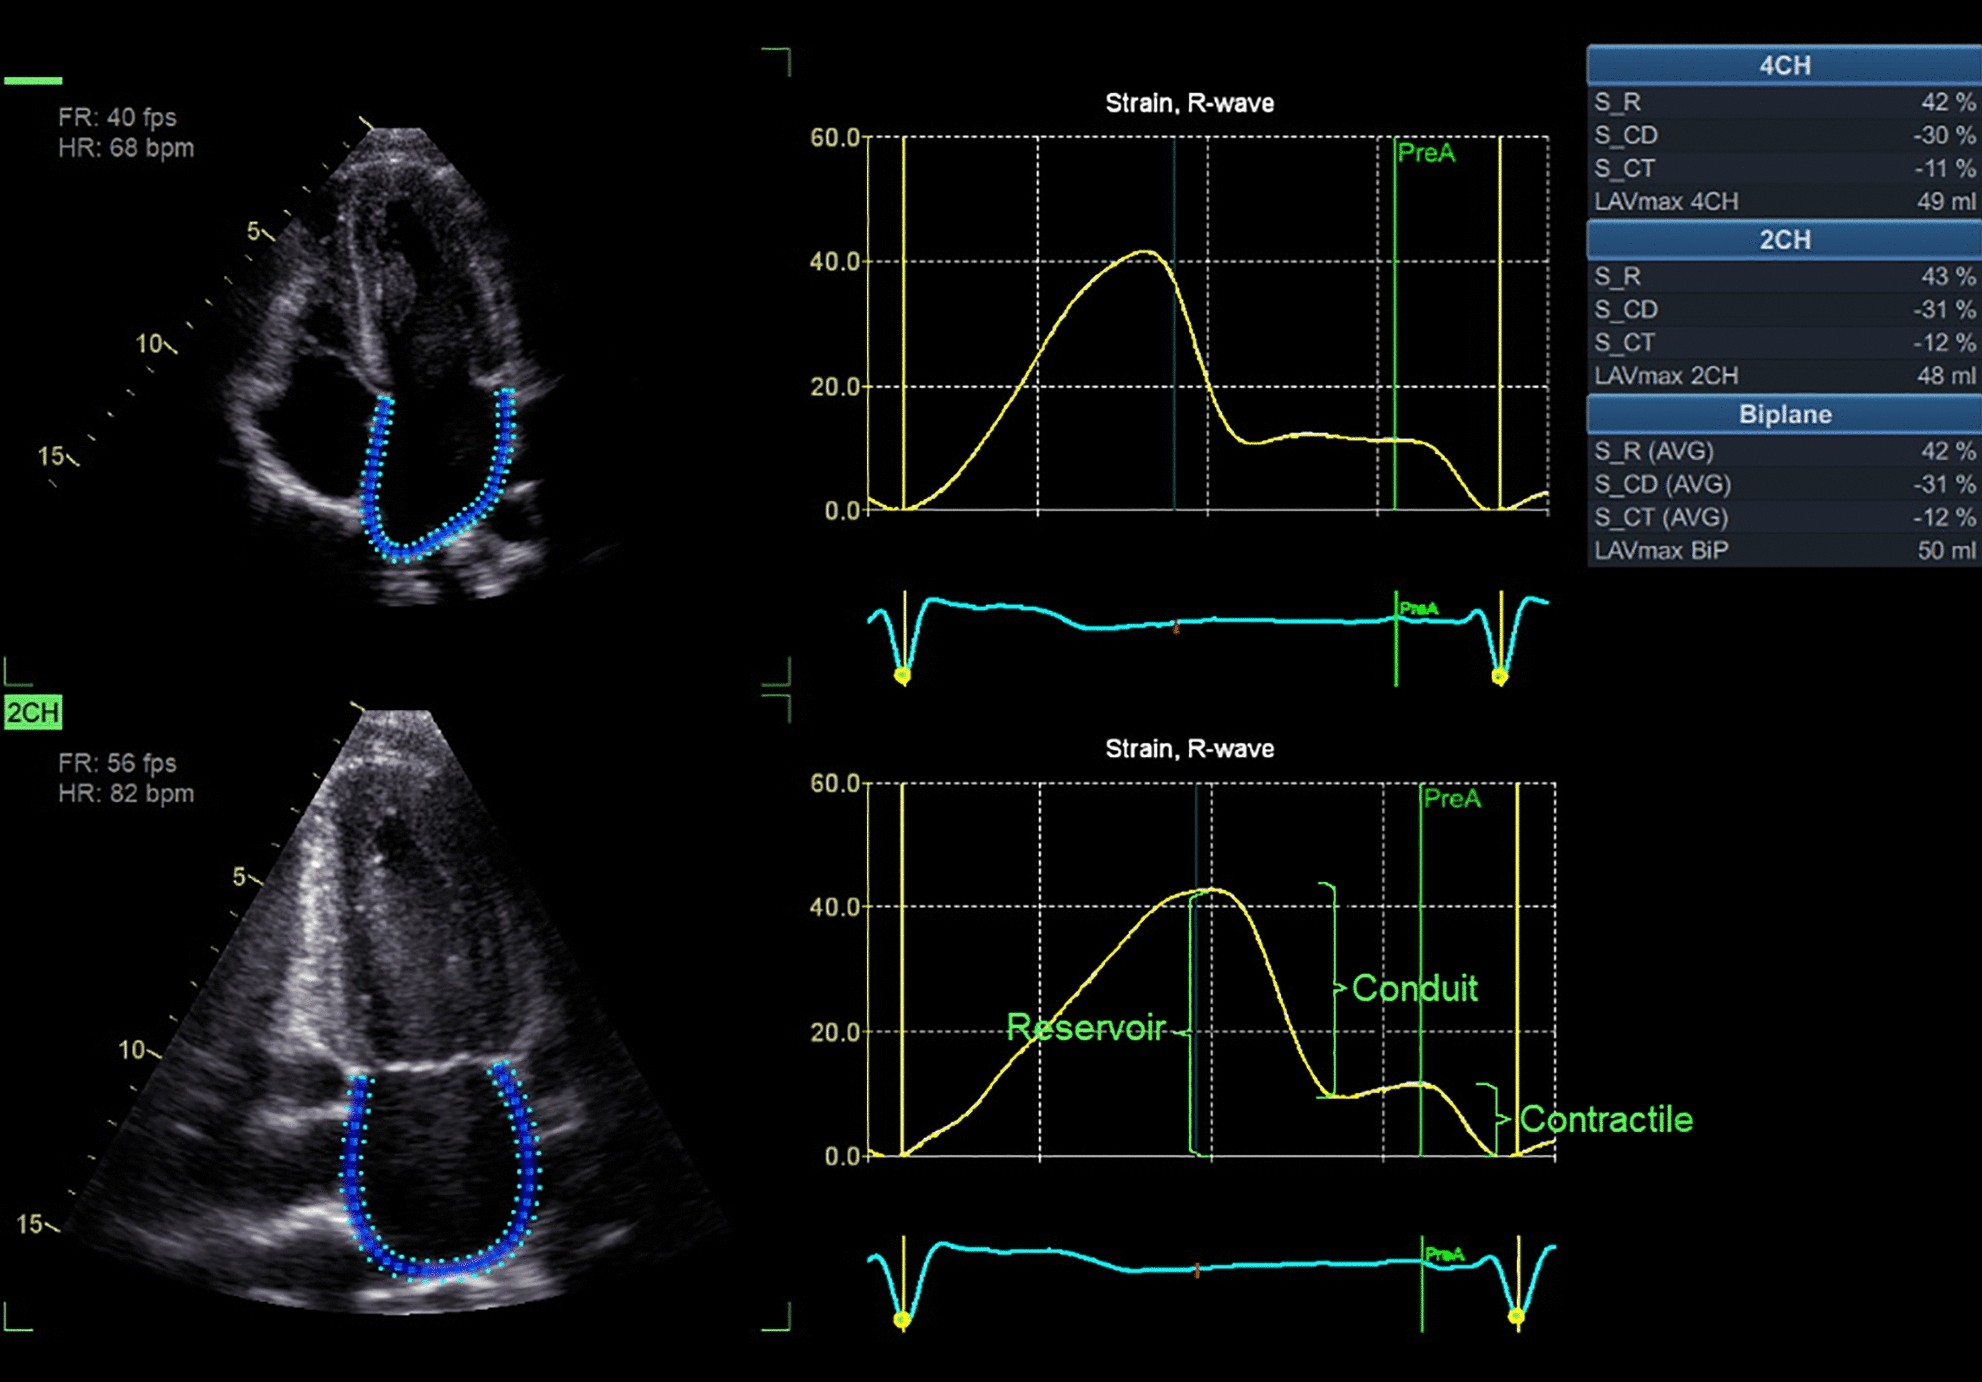

Figure 1

Strain analysis in 4- and 2-ch views, with the different phasic functions of LA strain (S): Peak atrial reservoir (S_R), conduit (S_CD) and contractile strain (S_CT) are presented in the table (upper right corner) for 4- and 2-ch views separately as well as a biplane average (Photo. Fridolfsson C).